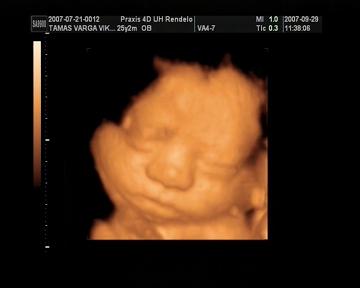

Megjöttünk az uh-ról. Jelentem óriásbébivel rendelkezem! Néhány adat a sok-sok közül: BPD: 8,84 cm AC:29,1 cm FL: 5,94 cm. Becsült súly: 2057 g. Mért adatok alapján becsült terhességi hét: 33.hét 5. nap. :) Úgyhogy Bendő két héttel előrébb jár kb. Viszont hosszban nem olyan hosszú, 40 cm körül van.

Azt mondta a doki bácsi, hogy teljesen egészségesnek tűnik és nagyon szép. Teszek fel képet!

Viki! Tényleg nagyon szép a kissrác! A második képen olyan, mintha magában mulatna valamin :wink: És a méretei nem semmik :shock: Látom, a Praxisban voltatok. Nagyon megbízhatóan, megnyugtatóan át szokták nézni a babákat, nem csak moziznak, és ez jó szerintem.

Varga Viki:Nagyon édes a kisfiad, a második képen mintha elmosolyodott volna.Mi szerdán voltunk ultrahangon a 32.héten járunk akkor volt 2130g és 42cm és azt mondt a doki, hogy átlagos baba, de szerintem óriás bébi lesz.Szedtél valami vitamint?

Meddig tartott a vizsgálat?Mi is voltunk a 30.héten fantasztikus élmény volt.